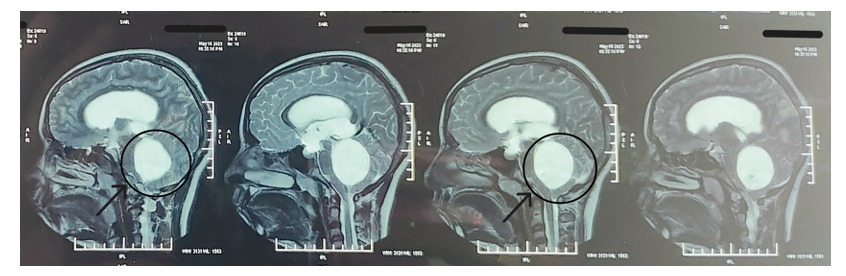

Accurate diagnosis is essential for effective AVM management:

- Clinical Examination: Neurological evaluation to assess deficits

- Imaging Studies:

- MRI & CT Scans: Map the AVM’s location and size

- Angiography: Provides a detailed view of blood flow and vessel structure

This ensures a personalized treatment plan that targets the AVM precisely while minimizing risks.